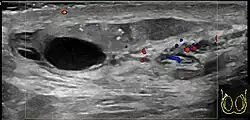

In those who are young and sexually active, gonorrhea and chlamydia are frequently the underlying cause.[1] In older males and men who practice insertive anal sex, enteric bacteria are a common cause.[1] Diagnosis is typically based on symptoms.[1] Conditions that may result in similar symptoms include testicular torsion, inguinal hernia, and testicular cancer.[1] Ultrasound can be useful if the diagnosis is unclear.[1]

Diagnosis is typically based on symptoms.[1] Conditions that may result in similar symptoms include testicular torsion, inguinal hernia, and testicular cancer.[1] Ultrasound can be useful if the diagnosis is unclear.[1]

Epididymitis usually has a gradual onset. Typical findings are redness, warmth, and swelling of the scrotum, with tenderness behind the testicle, away from the middle (this is the normal position of the epididymis relative to the testicle). The cremasteric reflex (elevation of the testicle in response to stroking the upper inner thigh) remains normal.[1] This is a useful sign to distinguish it from testicular torsion. If there is pain relieved by elevation of the testicle, this is called Prehn's sign, which is, however, non-specific and is not useful for diagnosis.[13] Before the advent of sophisticated medical imaging techniques, surgical exploration was the standard of care. Today, Doppler ultrasound is a common test: it can demonstrate areas of blood flow and can distinguish clearly between epididymitis and torsion. However, as torsion and other sources of testicular pain can often be determined by palpation alone, some studies have suggested that the only real benefit of an ultrasound is to assure the person that they do not have testicular cancer.[14]: p.237 Nuclear testicular blood flow testing is rarely used.